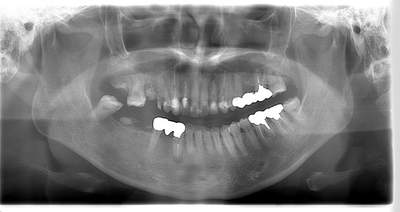

左上下の親知らずが

大きな虫歯になっていた症例

- 抜歯前写真(レントゲン)

- 抜歯前写真(CT画像)

| 年齢 | 20代・男性 |

|---|---|

| 主訴 | 奥歯が欠けて、痛みがある |

| 親知らずの生え方 | 完全に出ている、まっすぐ生えている |

| 抜歯時間 | 30分 |

| 費用 | 約5,000円 |

| 抜歯内容 | 奥歯が欠けて痛みがあるとのことで来院された患者様です。左上下の親知らずが大きな虫歯になっており、神経まで達している状態でした。上下ともに歯の頭部分は虫歯で脆くなっていたため、できるだけ根の部分の方に器具を引っかけて抜歯を行いました。 この症例では事前にCTを撮影し、歯の位置、根の方向、上顎洞との位置関係を確認していたため、上顎洞への穿孔や下顎の神経麻痺など後遺症も起こりませんでした。 抜歯後はほとんど腫れ、痛みはなく元々あったお痛みもなくなり患者様も安心しておられました。 |